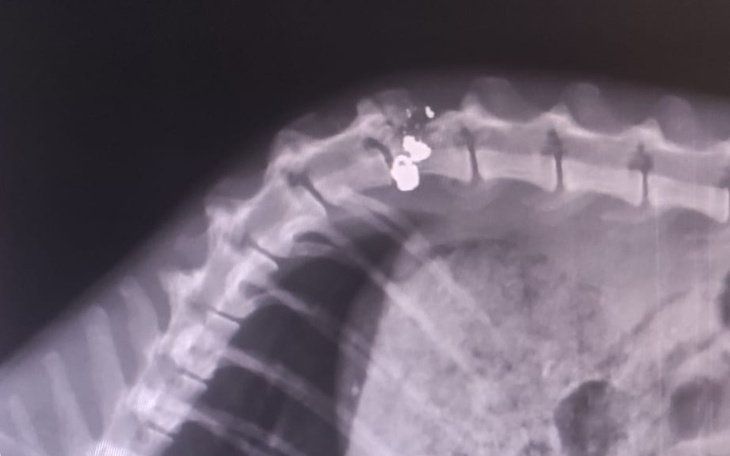

Dostał precyzyjnego strzała z broni śrutowej z bliskiej odległości. Śrucina utknęła idealnie przy kręgosłupie, rozwalając jeden z kręgów na szereg drobnych fragmentów. Patologiczni strzelcy wyborowi się k... znaleźli.

Kot ciągnie za sobą tyle łapki, nie wypróżnia się samodzielnie. Od czołgania się ma pozdzierane opuszki nóżek. Z uwagi na zachowane pewne elementy czucia głębokiego, czeka go badanie neurologiczne oraz pewnie TK lub rezonans za miliony monet. Przez jakiegoś debila 🤬🤬🤬